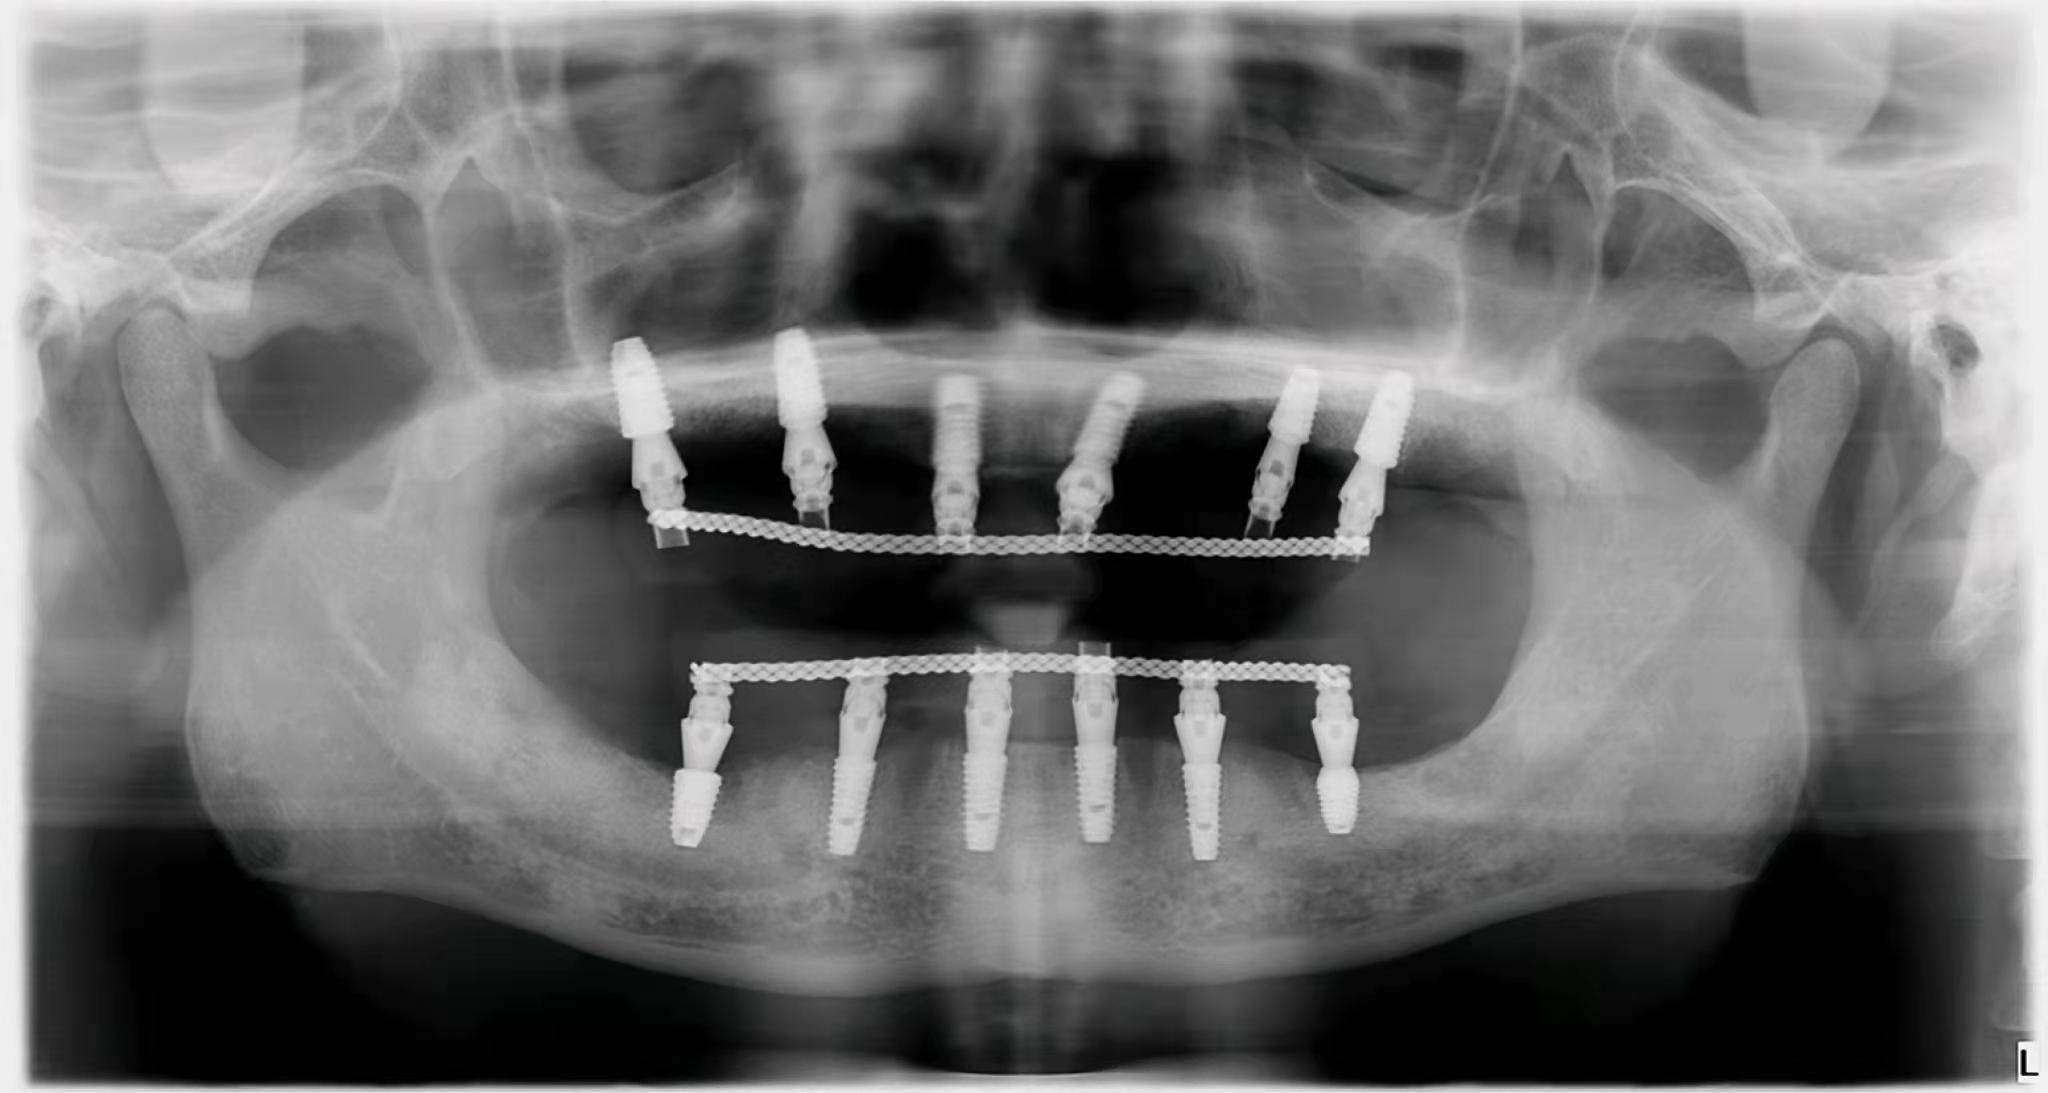

3. 種植牙價(jià)格降低在公立和私立口腔中,與種植體不同的是,國(guó)內(nèi)部分牙冠品牌已經(jīng)被大眾接受。如果是單顆牙缺失,預(yù)算有限,可以找醫(yī)生咨詢(xún)低成本方案。即使是全口或者半口牙缺失,需要種植,也不需要在牙窩上全部種植,可以用all-one-4,或者all-one-6。